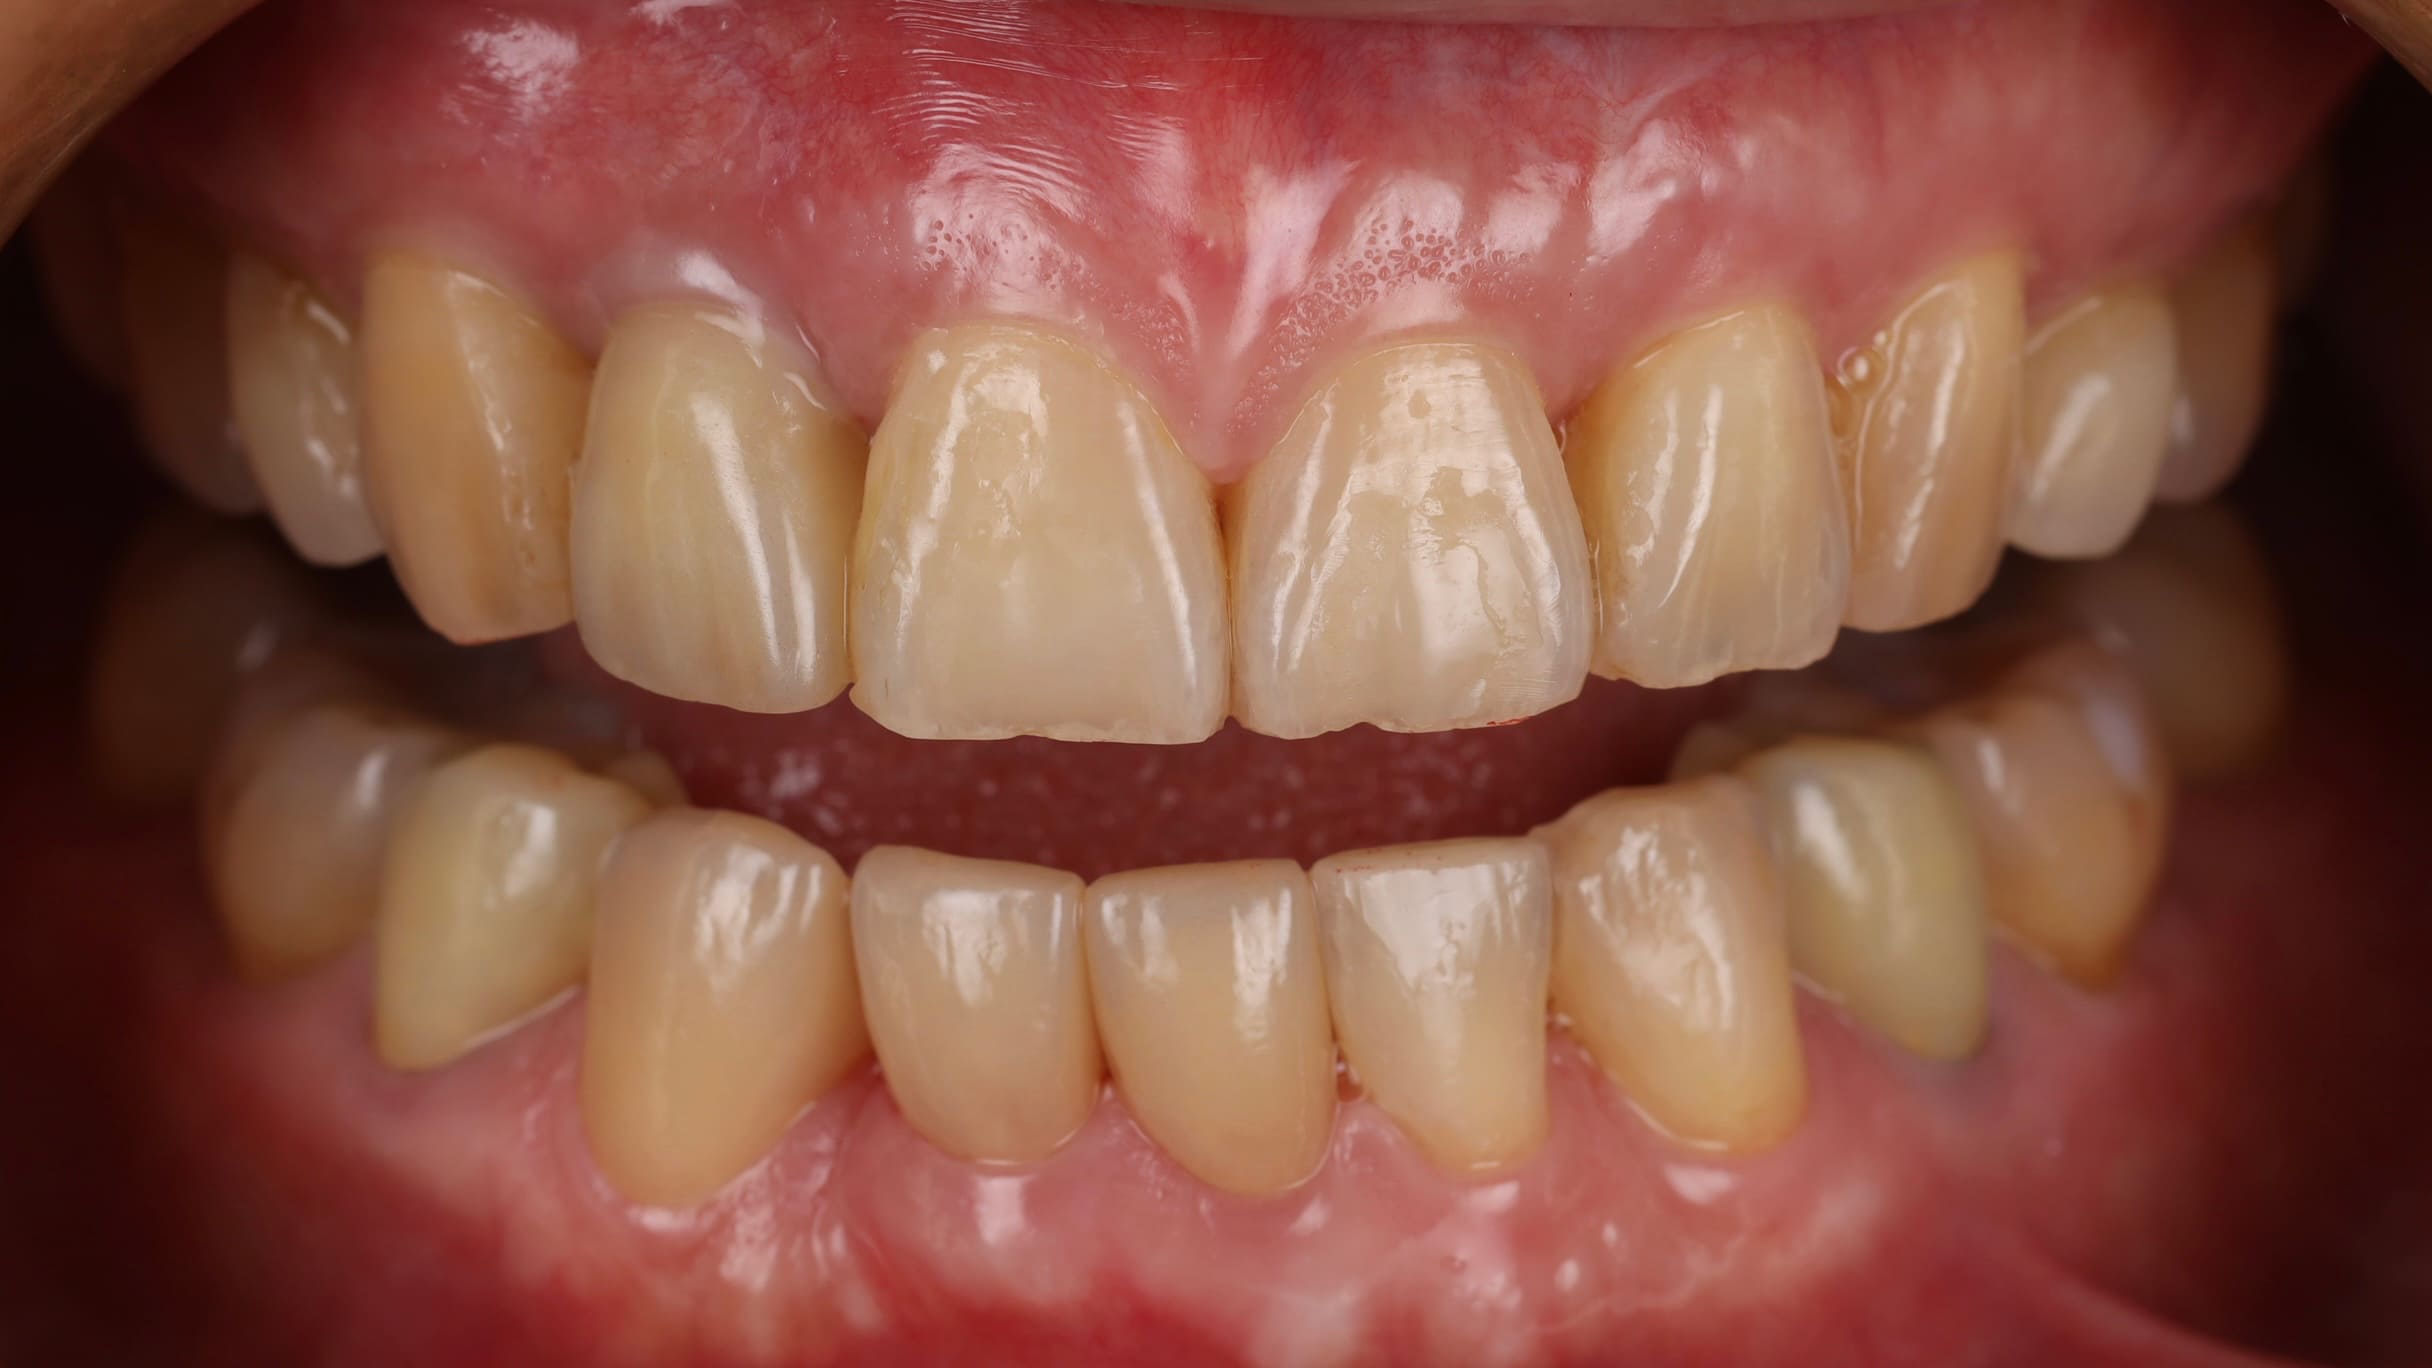

全瓷貼片解決黑三角問題

由於患者的牙齒天生形狀偏三角形,又因為牙周病造成牙齦萎縮。之前因為下排牙齒擁擠,這個問題並不明顯,但當矯正完成、牙齒排列恢復正常後,牙縫間的空隙反而特別顯眼。因此在整個治療的最後一步,我們利用全瓷貼片改變牙齒的形狀,讓牙齒變得更方正,並有效改善黑三角問題,達到整體外觀的和諧一致。

這位患者的完整治療歷程總共花了將近兩年半的時間,雖然治療時間較長,但患者對於最終的成果非常滿意,不僅恢復了口腔的健康,整體的笑容也更加和諧自然。在治療的每個階段,我們都會非常詳細地向患者說明,讓她能夠充分理解並放心地配合療程。這份信任與耐心,最終成就了這個令人滿意的結果。複雜的口腔狀況確實需要時間和耐心,但只要循序漸進、按部就班地治療,每個人都有機會重新找回屬於自己的完美笑容!